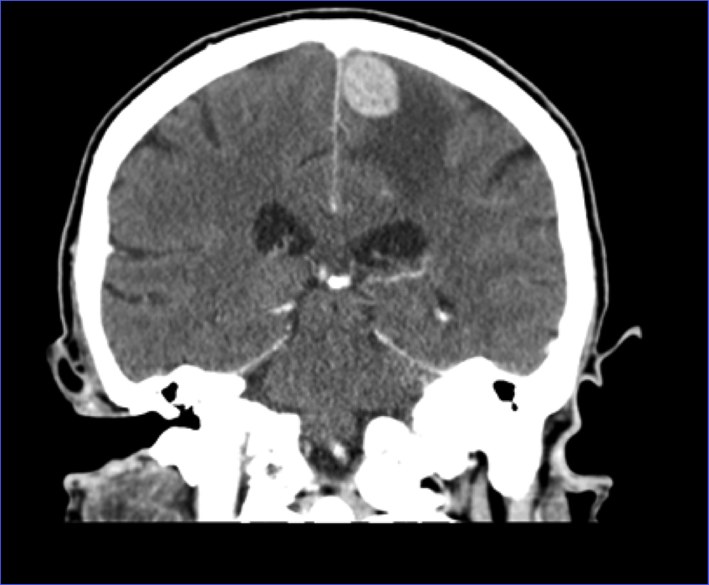

CT of head showed a left frontal 2.6 × 1.5 cm mass (Fig. 1, 2). MRI of brain done showed a 2.7 × 1.9 × 1.7 cm lobulated oval shaped mass located in left parafalcine posterior frontal area with perilesional edema with mass effect on precentral gyrus and effacement of central sulcus.

![]() Click for large image | Figure 2. CT of head coronal view showing left frontal mass with surrounding edema. |